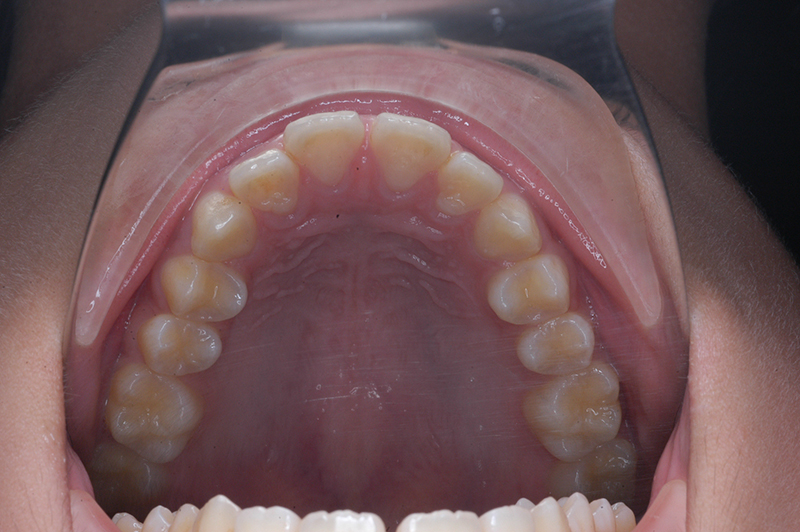

動的治療終了時

FP・IOP

批評・予后 上顎前歯舌側移動により上口唇形態は改善したこと、また動的治療中の下顎骨、特に下顎枝の成長が認められ下顔面高さは高くなったことが相俟って良好なプロファイルは得られたと思う。咬合の緊密化や歯根のパラレリングは行えたように思う。今後は第三大臼歯の萌出方向に注意を払い、頃合いを見計らって抜歯を検討している。